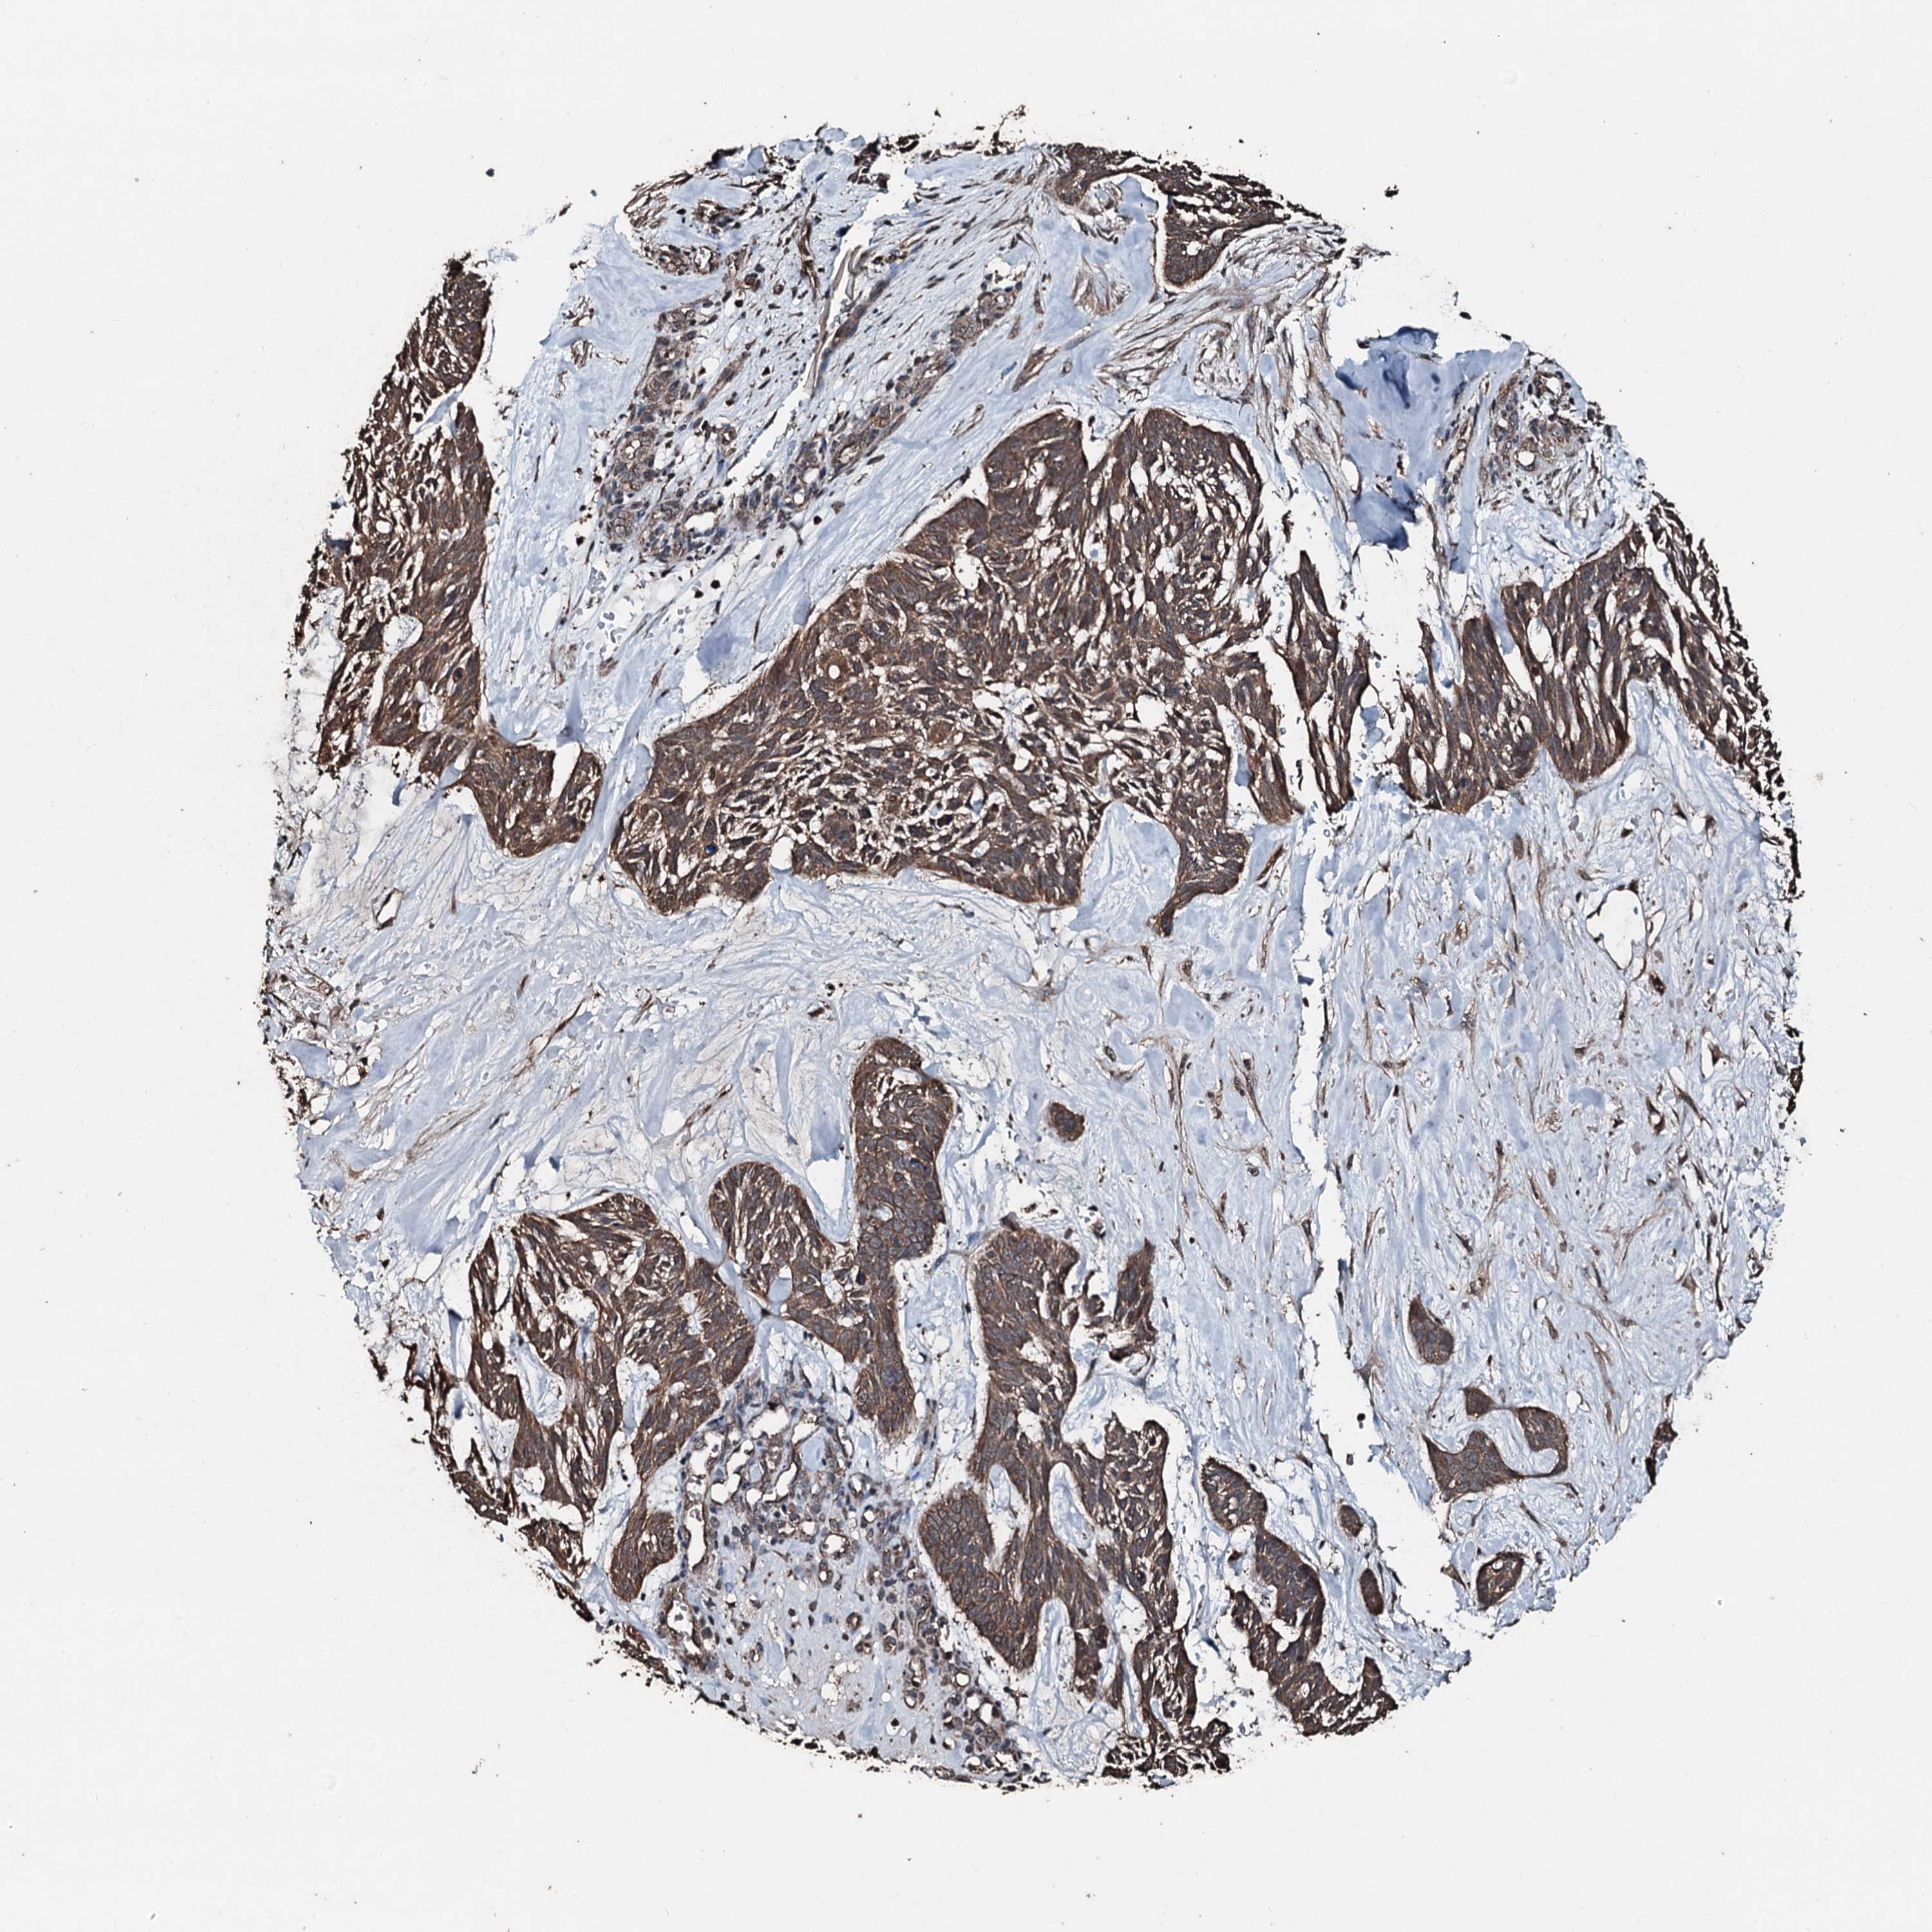

SKIN CANCER - Protein expressioni

A mouse-over function shows sample information and annotation data. Click on an image to view it in a full screen mode. Samples can be filtered based on level of antibody staining by selecting one or several of the following categories: high, medium, low and not detected. The assay and annotation is described here.

Antibody staining in the annotated cell types in the current human tissue is reported as not detected, low, medium, or high, based on conventional immunohistochemistry profiling in selected tissues. This score is based on the combination of the staining intensity and fraction of stained cells.

Each image is clickable and will lead to virtual microscopy that enables deeper exploration of all samples and also displays staining intensity scores, fraction scores and subcellular localization as well as patient and tissue information for each sample.

Antibody HPA041168

Basal cell carcinoma